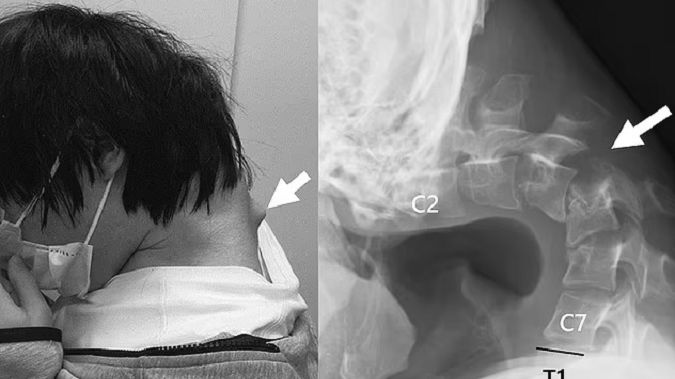

Lekarze nazwali jego przypadek "syndromem opadającej głowy", czyli skrajnym osłabieniem mięśni szyi, które sprawia, że głowa bezwładnie opada do przodu i nie może zostać utrzymana w pionie.

W tym czasie spędzał długie godziny grając na smartfonie, przez cały czas trzymając głowę w nienaturalnie pochylonej pozycji. Po sześciu miesiącach narastającego bólu karku i trudności z przełykaniem, młody mężczyzna zgłosił się do lekarzy.

Badania obrazowe wykazały deformację i przemieszczenie kręgów szyjnych oraz obecność zwłóknień i zbliznowaceń w obrębie kręgosłupa. Zdjęcia RTG ukazały dramatyczne zmiany – szyja była nienaturalnie wygięta, a kręgi przeciążone.